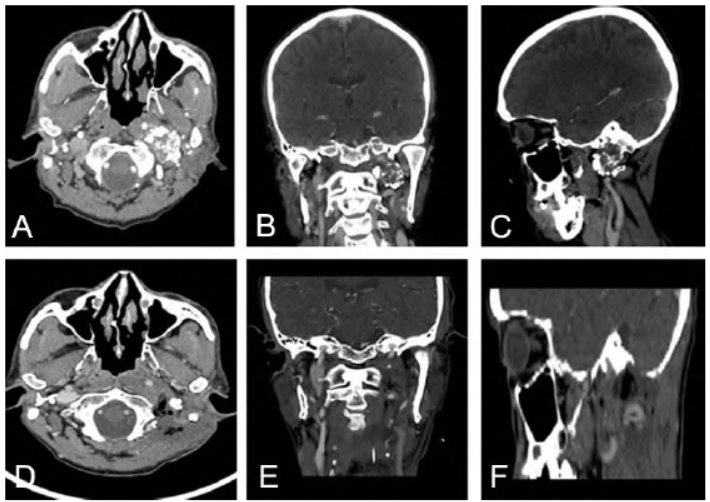

病例2:66岁男性,因声音嘶哑2个月、发现左侧JF区占位半个月于2021年10月2日入院。患者偶有饮水、进食呛咳。入院体格检查:左侧声带固定于旁正中位,右侧声带运动正常,伸舌稍偏向左侧。头颅MRI、CT示左侧口咽侧后壁、颈静脉孔区占位(图2A~C)。术前诊断:左侧JF区良性肿瘤。在导航辅助下显微手术切除JF区肿瘤,并行颅底重建。

术中见肿瘤部分起源于JF内,并未明显突入桥小脑角硬膜;肿瘤主体向前方咽旁间隙扩展,包膜完整、边界清晰,实质内多钙化组织。先部分切除肿瘤、获得空间后,沿边界分离,最终全切除肿瘤(图2D~F)。术后病理显示:高分化软骨肉瘤

(WHO 分级Ⅰ级),Ki67为3%。术后有轻度饮水呛咳、干咳,随访观察6个月,逐渐好转。

图2 左侧颈静脉孔区高分化软骨肉瘤手术前后影像。A~C. 术前头颅CT显示左侧颈静脉孔区占位性病变;D~F. 术后4个月复查头颅CT显示肿瘤无复发